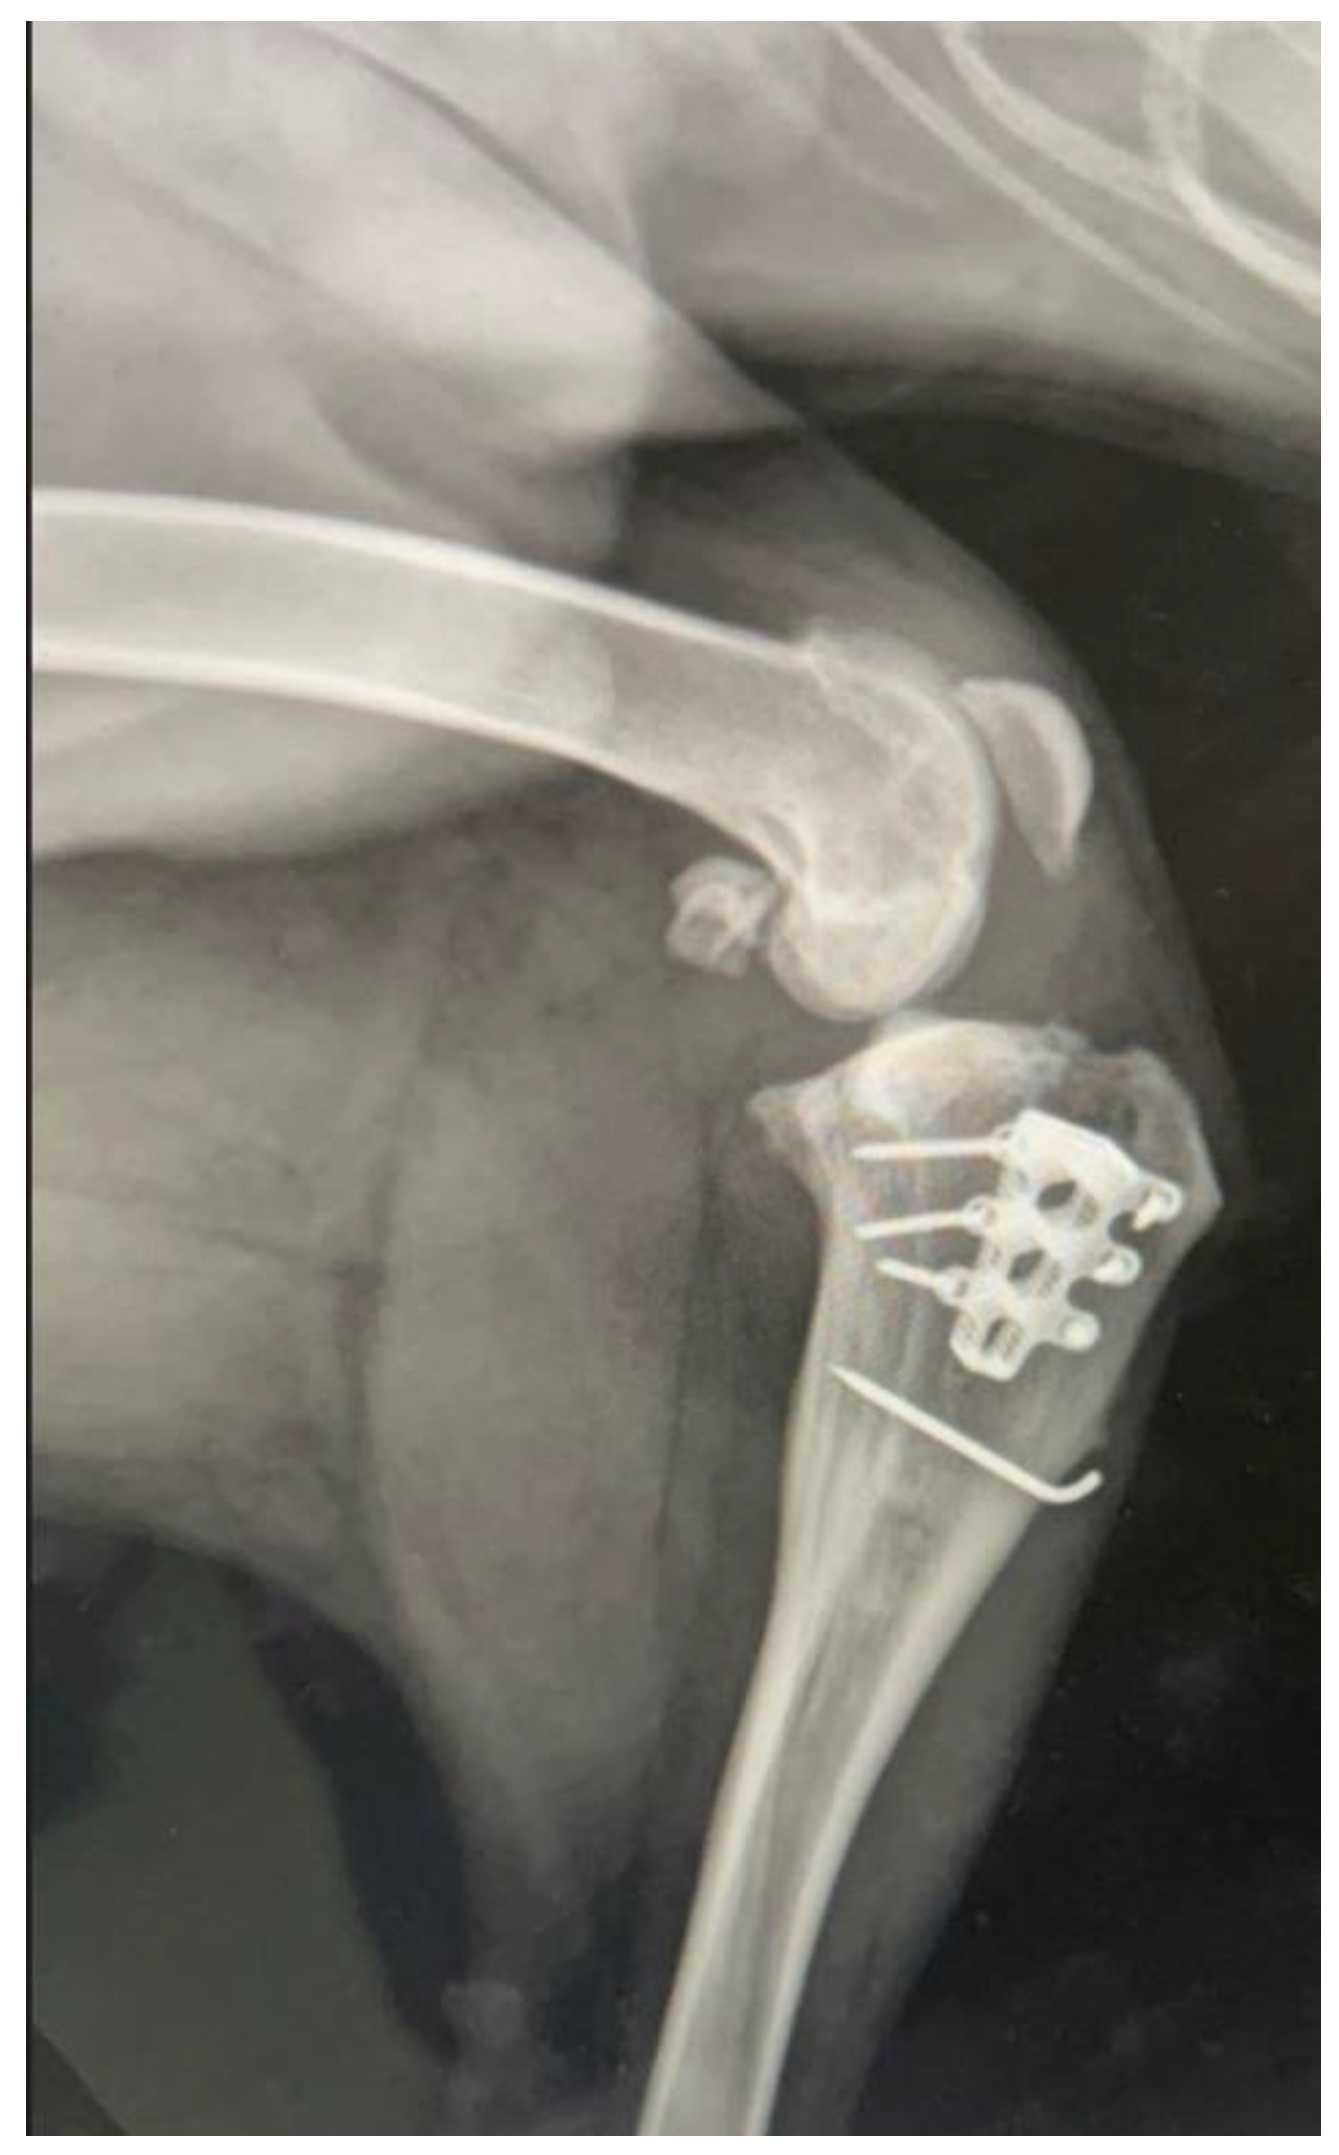

Modified Tibial Tuberosity Advancement Rapid in a Dog with One Contralateral Amputated Limb

2. Detailed Case Description